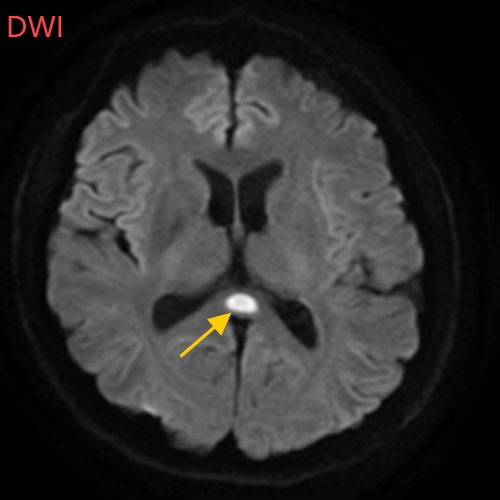

返深后,他出现了双手发抖、走路摇晃等状况,甚至出现幻听、意识模糊、记忆下降等症状,随后前往医院就诊,确诊为可逆性胼胝体压部综合征。

△董先生的影像结果显示胼胝体压部发生病变(图源:南方科技大学医院)

如果把大脑比作一座城市,胼胝体就是连接左右脑的“跨海大桥”,而胼胝体压部正是桥上的“核心枢纽”。当它因酒精、熬夜或感染“肿了”,大脑信号就会“堵车”,引发一系列“故障”。

“压部”发生病变后,就像电视机信号接收不良,屏幕出现雪花一样,眼睛视物就会受到影响。

除了“压部”,胼胝体的其他部位也有病变,所以董先生才会出现幻听、手抖等症状。